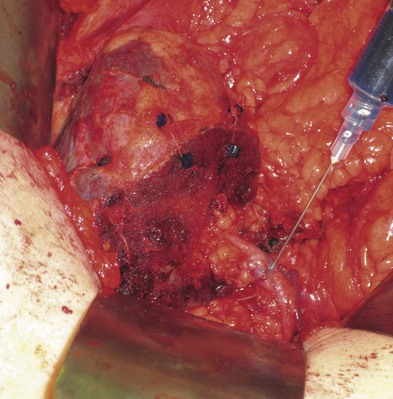

For large renal tumors, especially those of the upper pole, the thoracoabdominal approach is preferable to an anterior approach (Fig. 54–92; see Fig. 54–93 on the Expert Consult website

). On the right side the liver is retracted cephalad. The hepatic flexure of the colon and the duodenum are reflected medially, exposing the IVC, the renal pedicle, and the anterior surface of the kidney (Figs. 54-94 to 54-96). The renal artery and vein are handled as described for the anterior approach. The ureter and right gonadal vein are ligated and divided. The kidney is mobilized outside the Gerota fascia down to the psoas fascia. The additional vascular attachments to the upper pole tumor and adrenal gland are exposed by medial retraction of the IVC along with caudal and lateral retraction of the kidney. They are ligated and divided. A curved-shaped clamp is passed along the superior portion of the adrenal gland to gain control of the phrenic vessels using a 0 silk suture ligature. The specimen is mobilized fully away from the liver and removed en bloc.

Figure 54–94 Exposure of large right upper pole tumor through a thoracoabdominal incision.

(Reproduced with permission from Novick AC, Streem SB, Pontes E, editors. Stewart’s operative urology. 2nd ed. Baltimore: Williams & Wilkins; 1989.)